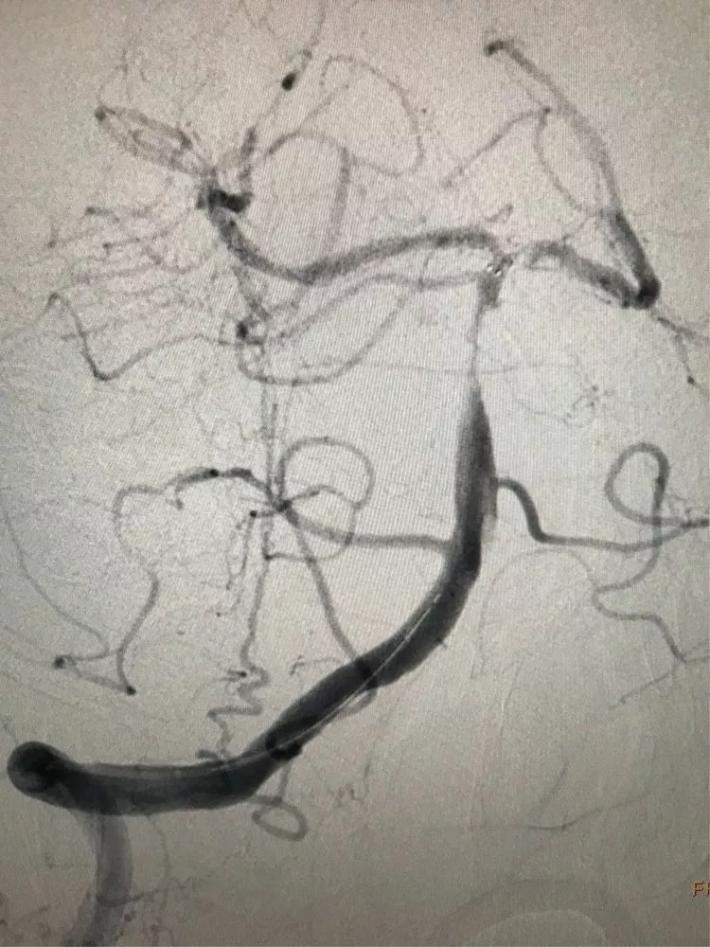

病例3

病史简介

患者女性,64岁。主因突发右侧肢体瘫痪3.5小时急诊入院。颅脑CT:未见出血。Nihss评分18分。急行静脉溶栓,同时MRA检查。

MRA显示:左侧颈内动脉闭塞。

手术步骤

立即桥接取栓,造影显示:左侧颈内动脉闭塞。

右侧颈内动脉向左侧没有代偿。

椎动脉造影显示后交通动脉没有代偿。

微导管进入左侧大脑中动脉远端真腔。

置入支架。

可见大脑中动脉有血流。

取出支架未见血管开通。

再次置入微导管。

置入支架取栓。

见颈内动脉开通,大脑中动脉远端有血栓逃逸。